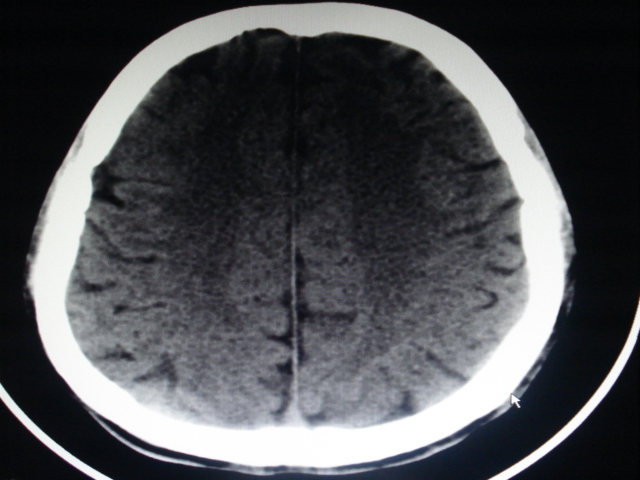

男性,48岁。发现右顶部包块一月余,质软有轻压痛。

其余没问题的层面我没有发上来,请教各位老师,可以考虑嗜酸性肉芽肿吗?